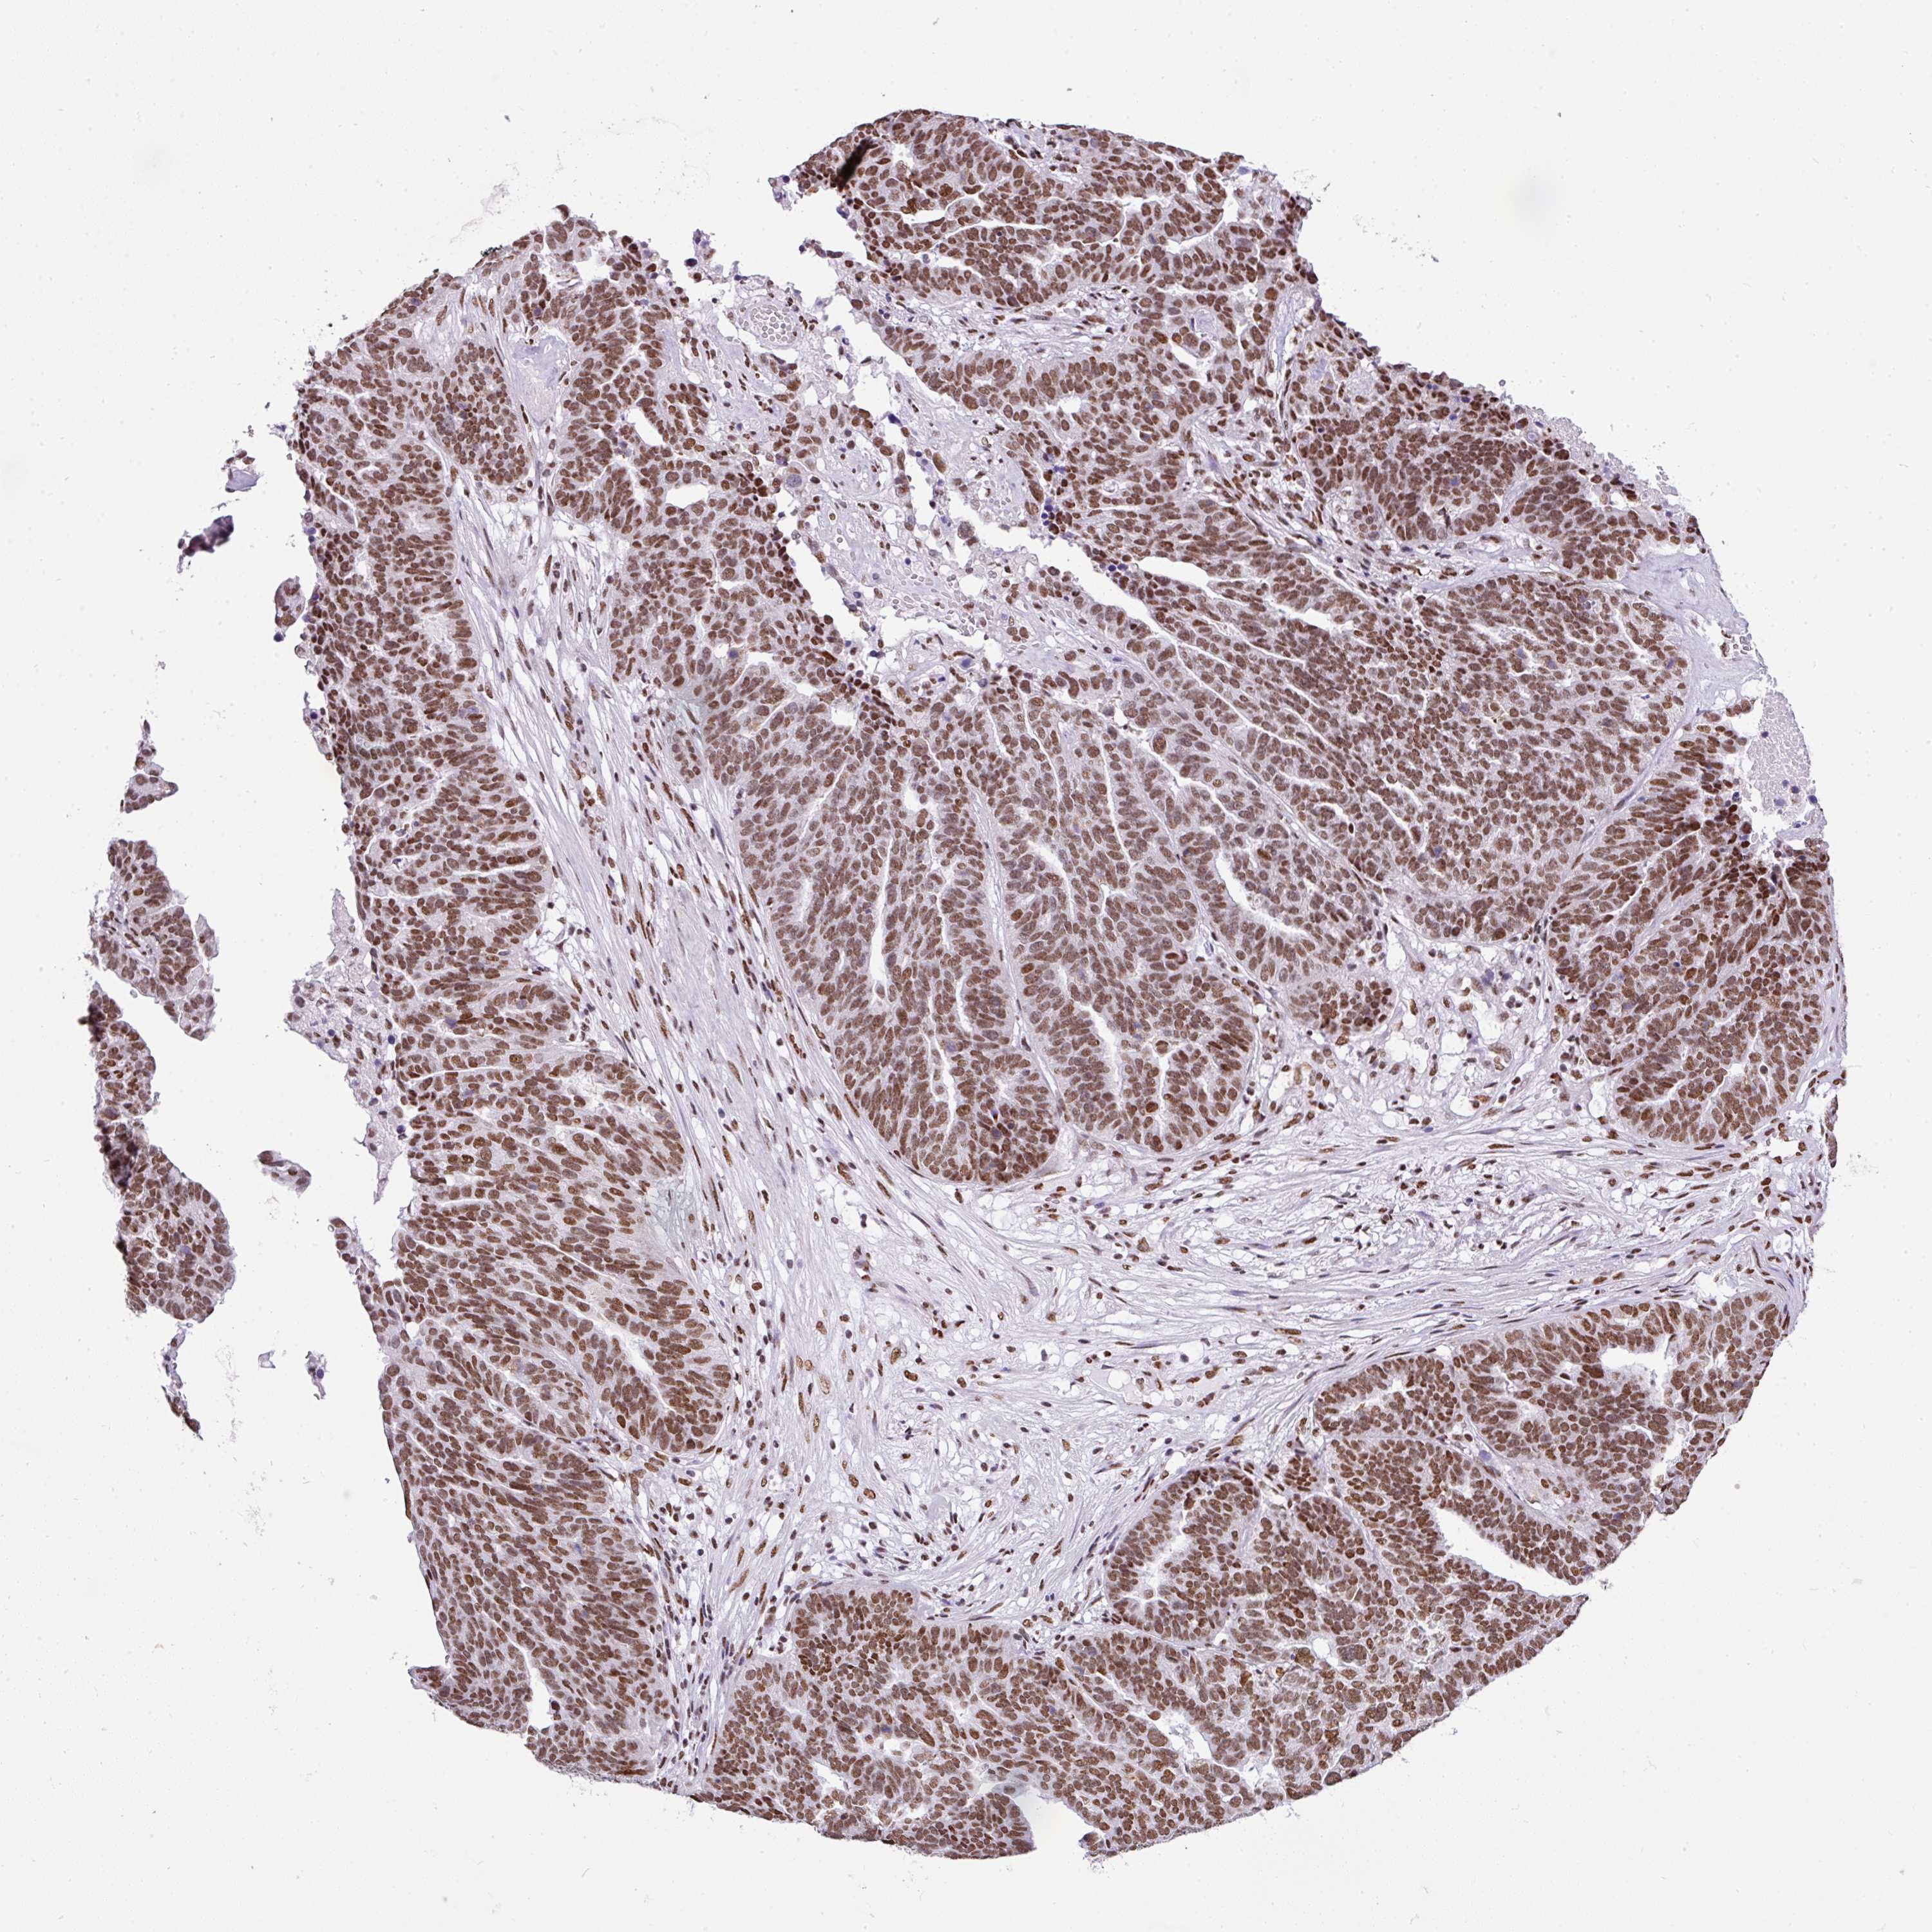

OVARIAN CANCER - Protein expressioni

A mouse-over function shows sample information and annotation data. Click on an image to view it in a full screen mode. Samples can be filtered based on level of antibody staining by selecting one or several of the following categories: high, medium, low and not detected. The assay and annotation is described here.

Note that samples used for immunohistochemistry by the Human Protein Atlas do not correspond to samples in the TCGA dataset.

Antibody stainingi

Antibody staining in the annotated cell types in the current human tissue is reported as not detected, low, medium, or high, based on conventional immunohistochemistry profiling in selected tissues. This score is based on the combination of the staining intensity and fraction of stained cells.

Each image is clickable and will lead to virtual microscopy that enables deeper exploration of all samples and also displays staining intensity scores, fraction scores and subcellular localization as well as patient and tissue information for each sample.

Antibody HPA053883

Staining

High

Medium

Low

Not detected

Intensity

Strong

Moderate

Weak

Negative

Quantity

>75%

75%-25%

<25%

None

Location

Nuclear

Cytoplasmic/membranous

Cytoplasmic/membranous,nuclear

Cystadenocarcinoma, serous, NOS

Carcinoma, NOS

Cystadenocarcinoma, mucinous, NOS

Carcinoma, endometroid